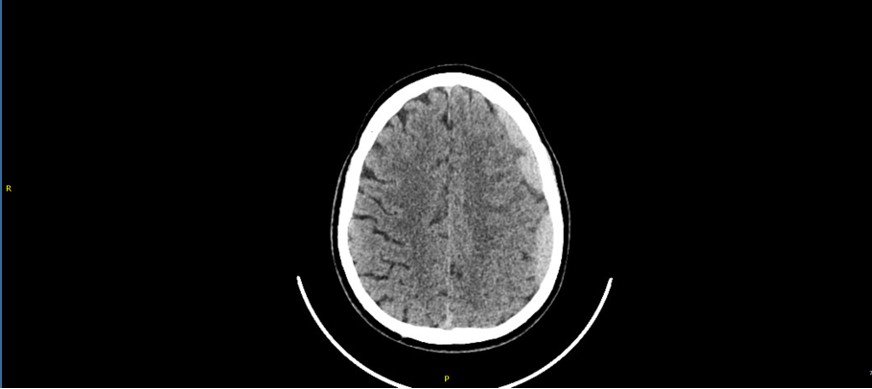

• TAC de cráneo: Hematoma subdural frontoparietal izdo, de probable evolución subaguda. Efecto de masa sobre parénquima cerebral, con obliteración de surcos de la convexidad izda, con mínimo desplazamiento de línea media (3 mm).

• Hematoma subdural frontoparietal izquierdo subagudo postraumático

Persiste colección hemática con puntos de resangrado. El paciente persiste pauci/asintomatico se plantea puede beneficiarse de embolización de meningea media.